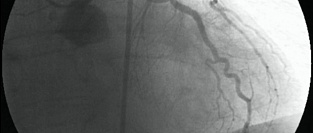

Незначимые поражения коронарных артерий и частота инфарктов миокарда

Результаты крупного анализа данных пациентов, получающих медицинскую помощь в учреждениях системы Ми...

11.11.2014 8441 #ИБС #ишемическая болезнь сердца #коронарография #инфаркт миокарда